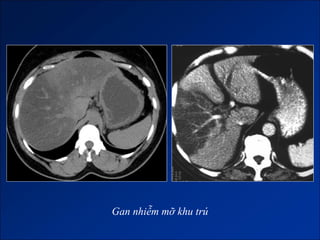

Hình ảnh trên CLVT

- Trước tiêm, tỷ trọng gan < tỷ trọng lách 10 HU.

- Các mạch máu trong gan hiện rõ.

- Sau tiêm, tỷ trọng gan < tỷ trọng lách 25HU or < tỷ trọng cơ.

- Gan nhiễm mỡ khu trú:

+ Thường ở HPT IV, cạnh dây chằng liềm.

+ Vùng nhiễm mỡ lan đến ngoại vi sát bao gan.

+ Không làm biến đổi bờ gan,

+ Không biến đổi cấu trúc mạch máu đi qua.

Gan nhiễm mỡ khu trú